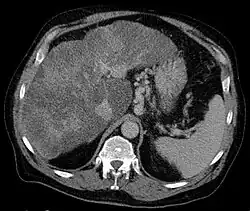

Gastric varices are dilated submucosal veins in the lining of the stomach, which can be a life-threatening cause of bleeding in the upper gastrointestinal tract. They are most commonly found in patients with portal hypertension, or elevated pressure in the portal vein system, which may be a complication of cirrhosis. Gastric varices may also be found in patients with thrombosis of the splenic vein, into which the short gastric veins that drain the fundus of the stomach flow. The latter may be a complication of acute pancreatitis, pancreatic cancer, or other abdominal tumours, as well as hepatitis C. Gastric varices and associated bleeding are a potential complication of schistosomiasis resulting from portal hypertension.

The Sarin classification of gastric varices identifies four different anatomical types of gastric varices, which differ in terms of treatment modalities:[1]

- Type 1 Gastroesophageal Varices: Esophagus extending to lesser curvature of stomach

- Type 2 Gastroesophageal Varices: Esophagus extending to greater curvature of stomach

- Type 1 Gastric Varices: Isolated to the fundus

- Type 2 Gastric Varices: Anywhere in the stomach, or duodenum

Type 1 isolated gastric varices were seen only in primary cases (i.e. without prior sclerotherapy) in the original study of Sarin et al. (1992), while type 1 gastroesophageal varices were the most common overall.[3]